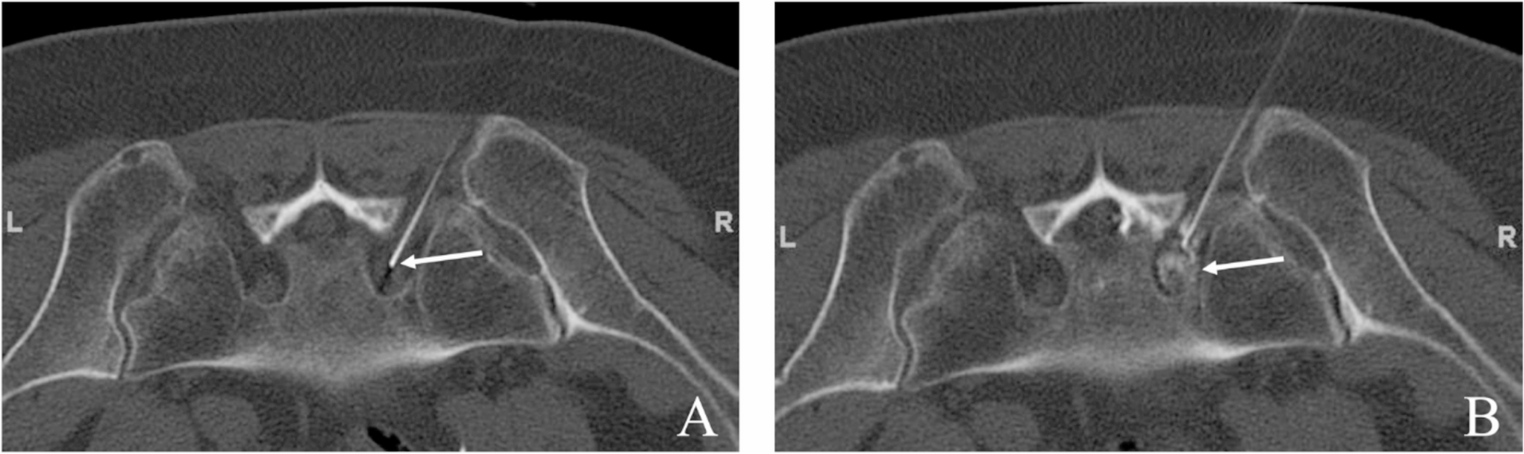

Comparison of brainstem hematoma volume evaluation techniques with a novel quantitative approach

This study systematically compares various methods for calculating brainstem hematoma volume, and introduces a novel estim...